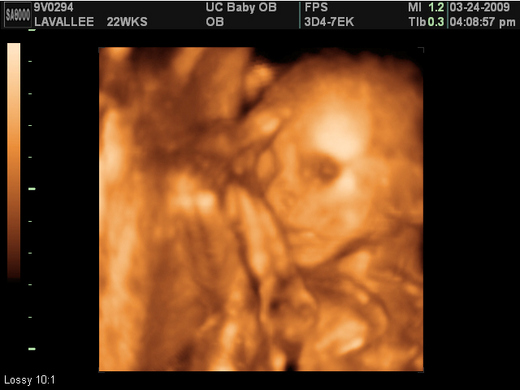

所以經過一翻掙扎後, 我和 Chris 決定放棄生產之後的 surprise. 自費去照4D 的超音波啦 !!

一開始我和 Chris 都以為是個男生, 然後診所的人才告訴我們我以為是小雞雞的東西其實是臍帶.

又過了十幾分鐘後, 終於確定是個 baby girl. 小 baby 已經有 Chris 的臉型. 只有眼睛像我, 其他都是 Chris 的翻版. 嘿嘿.... 有點不太甘心的感覺 !!